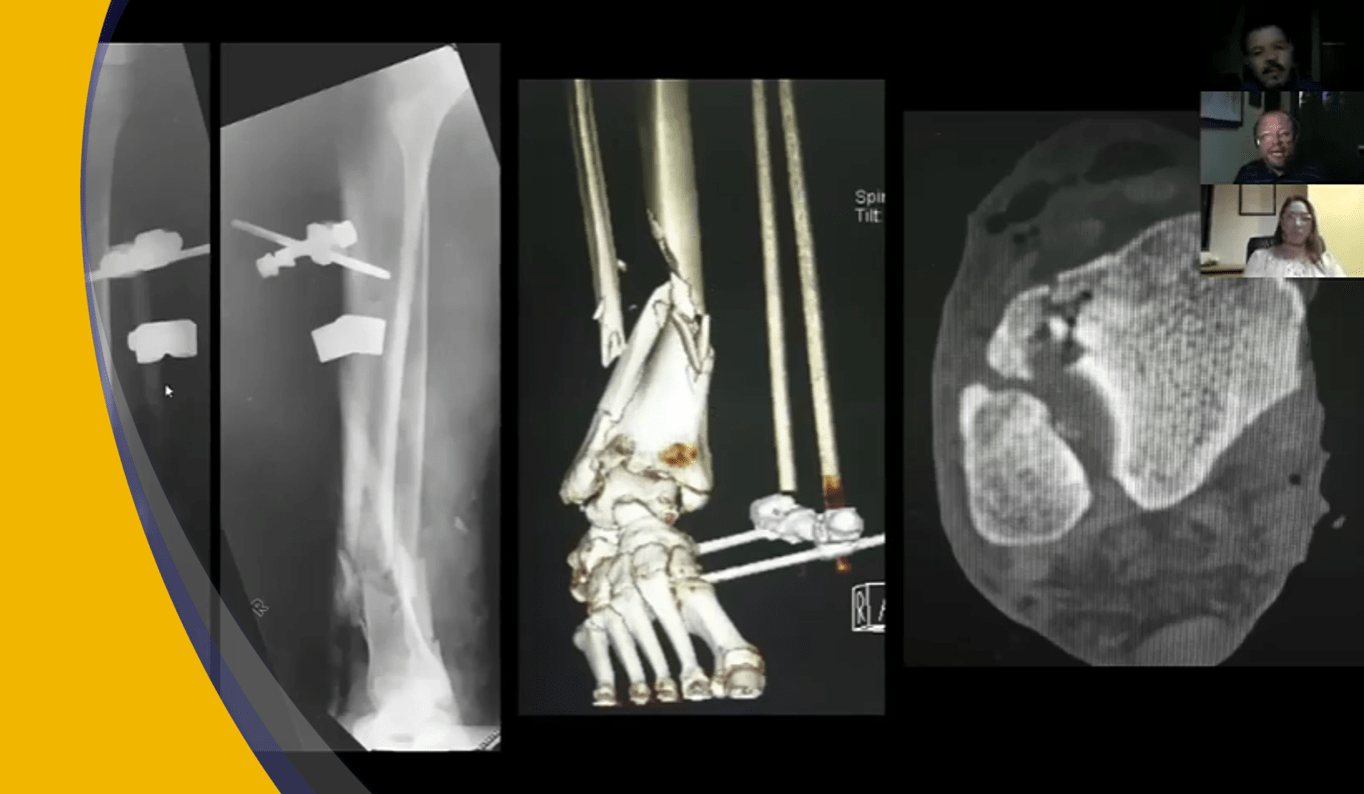

En el webinar el ponente compartirá una serie de casos de estudio donde se evidencian los resultados obtenidos ante determinadas prácticas, que se creían incorrectas o que no tenían efecto en el paciente durante el diagnóstico y tratado de una fractura.

Se denominan fracturas abiertas aquellas lesiones en las que el hueso roto, rompe la piel que recubre el miembro. Este tipo de lesión ósea debe ser tratada cuanto antes debido a que el sistema vascular puede verse comprometido en este tipo de accidentes.

Debido a su naturaleza, las fracturas abiertas pueden desencadenar en hemorragias, por lo que durante los primeros auxilios, se debe asegurar que no se comprometa la salud del paciente ante una gran pérdida de sangre. Antes de realizar algún movimiento se debe inmovilizar la parte del cuerpo comprometida, esto debe efectuarse a través de miembros de asistencia ortopédicos. De esta manera, se estabiliza la condición del paciente para su pronta evaluación.

Las fracturas abiertas deben ser cuidadosamente diagnosticadas, se requiere conocer las dimensiones, ubicación y el grado de afectación, ya que el movimiento óseo puede llevar a perjudicar algunos órganos internos. Para evitar la propagación de infecciones se debe retirar cualquier fuente contaminante como lo puede ser restos de basura, tierra, ropa rasgada u hojas. Complementa tu información sobre manejo de fracturas con nuestro artículo sobre técnicas básicas de primeros auxilios.

Clasificar este tipo de heridas es vital para iniciar el procedimiento o tratamiento. Existen varias bibliografías que pueden indicar la gravedad del tipo de hallazgo. Sin embargo, en la actualidad se utiliza la clasificación de Gustilo y Anderson, la cual describió que las fracturas abiertas pueden ser de tres tipos según su incidencia.